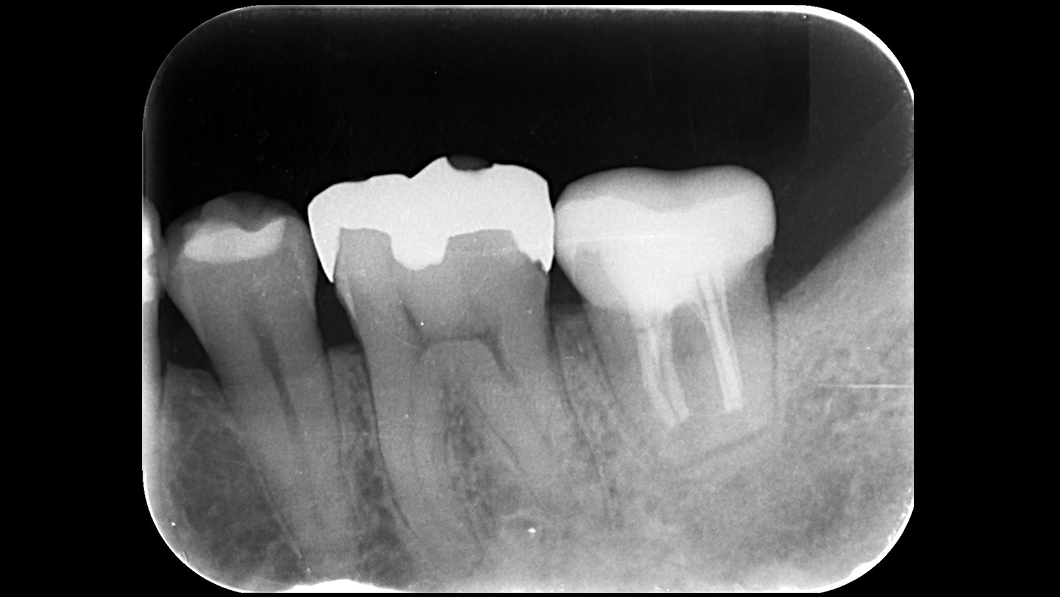

意図的再植

- 補綴物除去後歯牙を一度抜歯。口腔外で根切および根管形成を行い逆根管充填後口腔内へ戻し固定。

動揺落ち着いたのを確認後CAD/CAM冠にて補綴

- 術中:抜歯時に歯根破折の可能性

術後:歯根吸収(置換性吸収)、付着の部分的非獲得(部分的な深いポケットの形成)